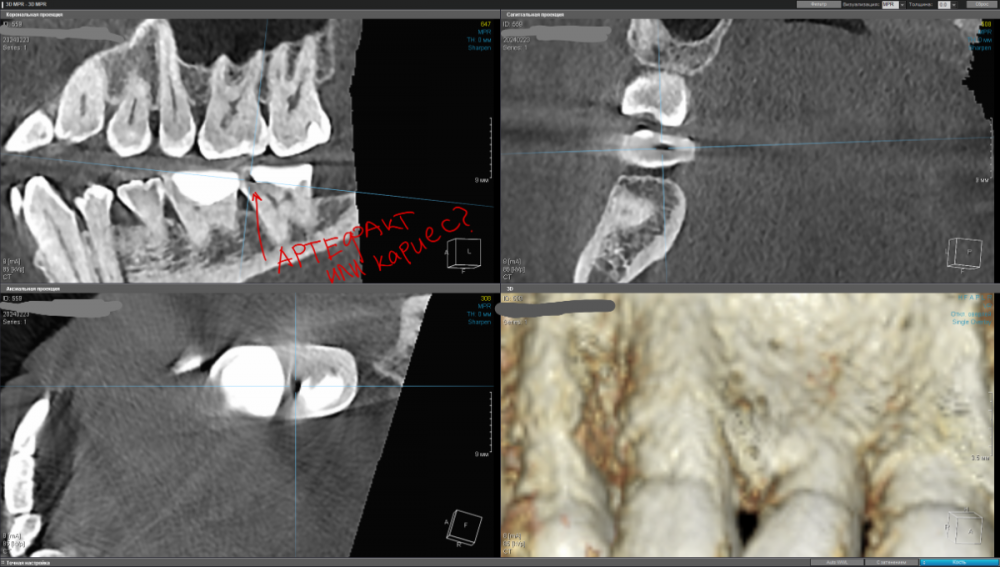

kamacho Опубликовано 24 февраля, 2024 Автор Поделиться Опубликовано 24 февраля, 2024 Попробую привлечь ваше внимание дополнительными снимками. Вопросы которые я себе задаю когда смотрю на КТ: 1) Между 14 и 15 зубом, это убыль фуркации или артефакт при съемке кт ? 2) В районе 37 ого зуба это артефакт или кариес ? Я пытаюсь санировать ротовую полость уже наверное лет пять, и никогда не удается решить проблему. Прошел множество клинник (наверное штук 5-6, включая 1 зарубежную). Но после попыток лечения, возникает одна и таже проблема, как только начинаю добавлять углеводы(не сладости) в рацион, какой-то очаг инфекции дает о себе знать. Буду очень признателен если поможете советом или догадкой. Ссылка на комментарий

kamacho Опубликовано 24 февраля, 2024 Автор Поделиться Опубликовано 24 февраля, 2024 (изменено) Так же приложу документ-опись риентгенолога по всем зубками с изображениями. снимок был сделан в 22 году. Наврятли кто-либо захочет перечитывать такое количество информации ради развлечения. Но для истории добавлю. Изменено 24 февраля, 2024 пользователем kamacho Ссылка на комментарий

Carioznik Опубликовано 25 февраля, 2024 Поделиться Опубликовано 25 февраля, 2024 15.02.2024 в 18:43, kamacho сказал: есть ли показания для лечения этого зубика? По идее есть, но нужно разбираться 15.02.2024 в 18:43, kamacho сказал: Могут ли не до конца пролеченные корни вызывать такую симптоматику ? Нет 17 часов назад, kamacho сказал: Между 14 и 15 зубом, это убыль фуркации Нет. Похоже, что на 14 есть кариес. Возможно это и причина кровоточивости и запаха. Но нужно смотреть настоящую КТ , а не скрины. 18 часов назад, kamacho сказал: районе 37 ого зуба это артефакт или кариес ? Больше на артефакт похоже, но это не точно: нужно смотреть настоящую КТ , а не скрины 1 Ссылка на комментарий